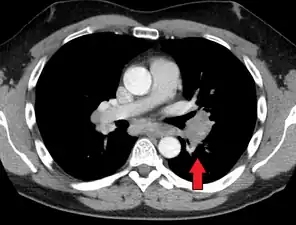

Hilar adenopathy especially on the person's left (transverse CT)